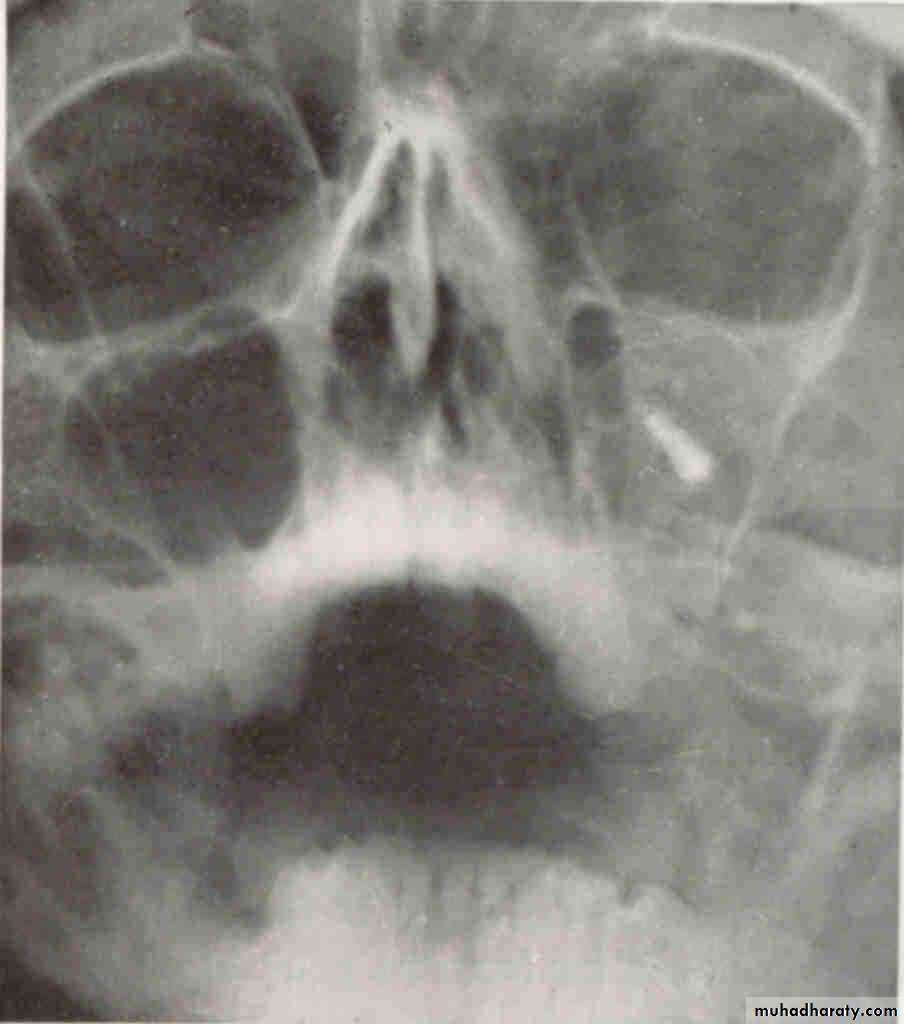

WATERS VIEW(Occipitomental )

premolar filmIs the radiopaque object identified by the arrows located on the buccal or the lingual?

6

Lingual. The tube head moves mesially from the premolar film to the canine film. The object also moves mesially, starting out distal to the first molar on the premolar film and ending up mesial to the first molar on the canine film. This object represents the tip of the palatal root of the second molar and is located distal to the first molar and in a lingual relationship